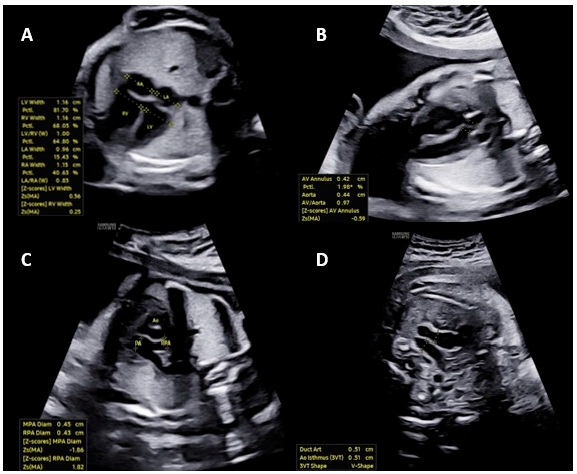

The Myocardial Performance Index (MPI) has been defined as a quantitative tool for the non-invasive assessment of the overall systolic and diastolic performance of the heart in adults and children and in cases of dilated cardiomyopathy [28]. MPI has been widely used in the literature to assess cardiac function in various pregnancy complications, including fetal growth restriction, twin-to-twin transfusion syndrome (TTTS), congenital diaphragmatic hernia, fetuses of diabetic pregnant women and fetal inflammatory response syndrome [29]. MPI can be defined as the ratio between the duration of the isovolumetric contraction time (ICT) and isovolumetric relaxation time (IRT) and the duration of the ventricular ejection time (ET), represented by the formula MPI = (ICT + IRT)/ET. Abnormal cardiac function has been demonstrated to be associated with a prolongation of the ICT and a shortening of the ET, resulting in an increase in MPI [30].

Kim et al. [31] conducted a prospective study, including normal singleton pregnancies between 16 and 38 weeks of gestation to establish reference ranges for fetal right ventricular modified MPI using MPI+™. Two experienced operators measured the right ventricle modified MPI using the automated and manual methods. A total of 364 examinations from 272 fetuses were analyzed for developing the references ranges. The modified MPI and IRT time increased throughout the gestational weeks. The ICT increased until 24 weeks of gestation and then slightly decreased afterwards, and the ET also increased until 31 weeks of gestation and then decreased. The automated system demonstrated significantly higher intra- and inter-operator reproducibility of modified MPI in comparison of manual measurements (ICC = 0.962 vs. 0.913 and 0.961 vs. 0.889, respectively).

Scharf et al. [32] performed a prospective study involving 85 normal fetuses between 19 and 36 weeks of gestation and the modified right ventricle MPI was measured, both by a beginner and an expert using the MPI+™. The mean right ventricle modified MPI value of the beginner was 0.513 ± 0.09, and that of the expert was 0.501 ± 0.08. Between the beginner and the expert, the measured right ventricle modified MPI values indicated a similar distribution. The ICC was 0.624 (95% CI, 0.423 to 0.755) (Fig. 3).

Figure 3: Automated modified myocardial performance index measurement using the MPI+™.